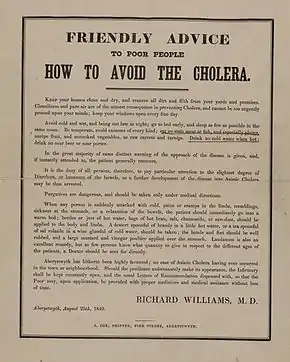

Emperor Pedro II of Brazil visiting people with cholera in 1855. Hand bill from the New York City Board of Health, 1832—the outdated public health advice demonstrates the lack of understanding of the disease and its causative factors.

Hand bill from the New York City Board of Health, 1832—the outdated public health advice demonstrates the lack of understanding of the disease and its causative factors.